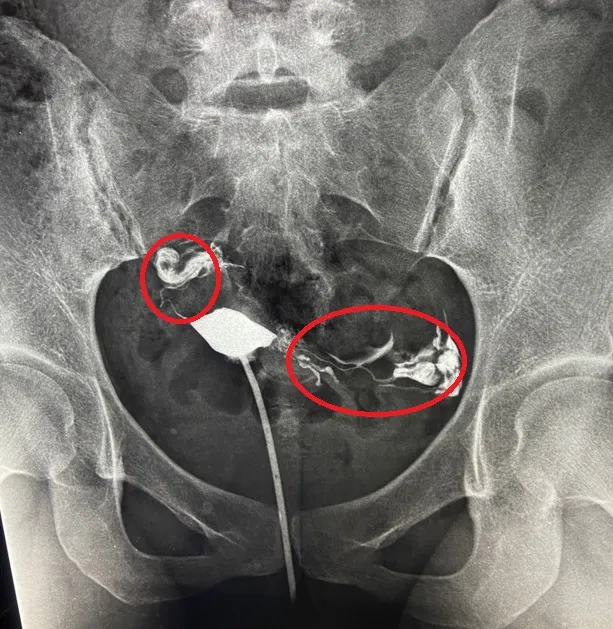

李小姐的輸卵管雙側都阻塞。茂盛醫院提供

李小姐和先生更求助信仰多年的神明,神明指示他們「去做試管吧!」於是到台中茂盛醫院尋求幫助。醫院檢查發現李小姐雙側輸卵管都有部分阻塞的現象,李茂盛院長立即為她安排試管療程。